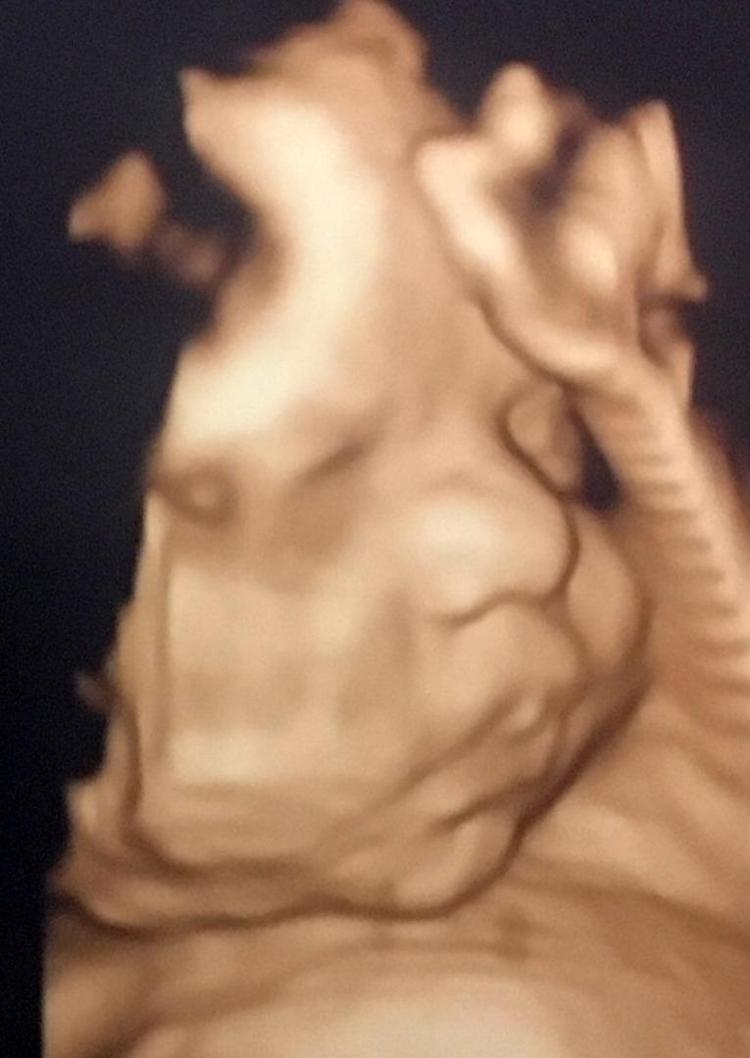

HaberlerFoto Galeri Haberleri Anne karnındaki bebeklerin gülümseten pozları Anne karnındaki bebeklerin gülümseten pozları. • Son Güncelleme: 20 Şubat 2020 - 09:11 • Son Güncelleme: 20 Şubat 2020 - 09:111 23456789101112